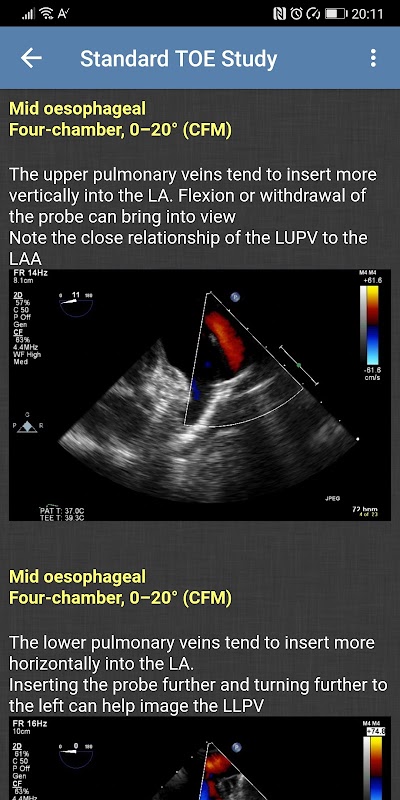

- دراسة TOE القياسية